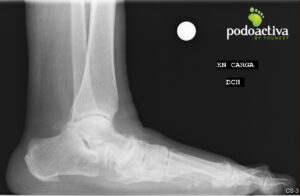

Mujer de 70 años acude refiriendo molestias a nivel del arco interno con evolución de 7 meses y no mejora con reposo ni antinflamatorios.

Se observa pie plano grado IV y lesión del ligamento de Spring. Se realiza exploración biomecánica y se observa una marcha en supinación compensando las molestias del arco interno. Tras el test biomecánico, indican alteraciones en la articulación subtalar y en los elementos estabilizadores del arco plantar.

Finalmente, el diagnóstico es un pie plano adquirido del adulto que cursa con lesión del ligamento de Spring y alteración del músculo tibial posterior.

Se pauta tratamiento mediante la realización de plantillas personalizadas utilizando la metodología de obtención de molde 3D Scan Sport Podoactiva® en carga controlada para evitar hipercorrecciones.